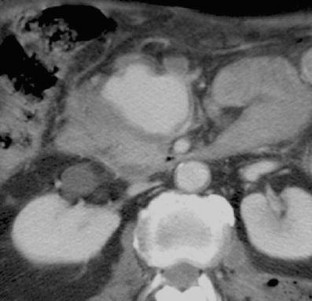

Combined percutaneous thrombin injection and endovascular treatment of gastroduodenal artery pseudoaneurysm (PAGD): case report

A 69-year-old man with a history of acute pancreatitis developed a huge pseudoaneurysm of the gastroduodenal artery (PAGD), as diagnosed by CT scan. The PAGD was treated by percutaneous thrombin injection (2,000 IU) under ultrasound guidance and selective embolization of gastroduodenal artery with microcoils with its complete exclusion. The 6-month follow-up confirmed the complete exclusion of the PAGD sac.

Fig. 1